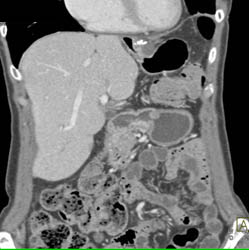

Diagnosis

Gastric Cancer